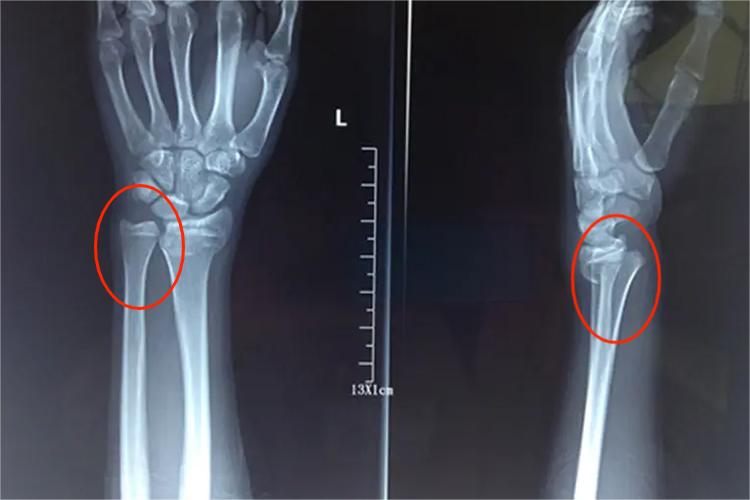

左手手腕X光片如果出现异常表现,可能是发生了骨折等病理情况。如桡骨远端骨折Colles骨折较为常见,典型的X线表现为远端骨折块向背侧、桡侧移位,骨折块旋后、骨折向掌侧成角、桡骨短缩。同时掌倾角呈负角,尺偏角变小。